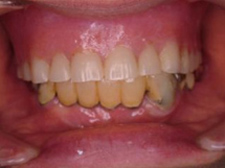

初診

【主訴】

・入れ歯の調子が悪く食べ物をよく咬めない

・下の歯がグラグラする

【正面観】